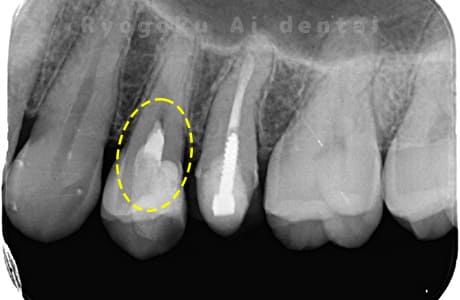

違和感があるとのことでレントゲン撮影を行なったところ、プラスチックの被せ物の中で虫歯が広がっていると判断。レントゲンの状態からも神経にかなり近いため、患者様と相談し、断髄治療を行なったケースです。3年間のフォローアップ期間中で現在トラブルはなし。